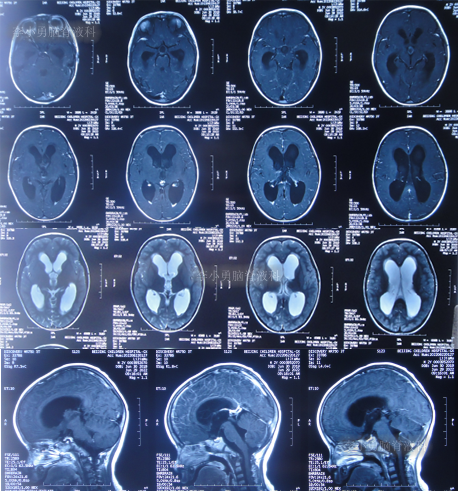

但该院治疗12天即2022年6月29日,复查头颅核磁脑室扩张进一步加重(图-6)。

图-6:2022年6月29日头颅核磁